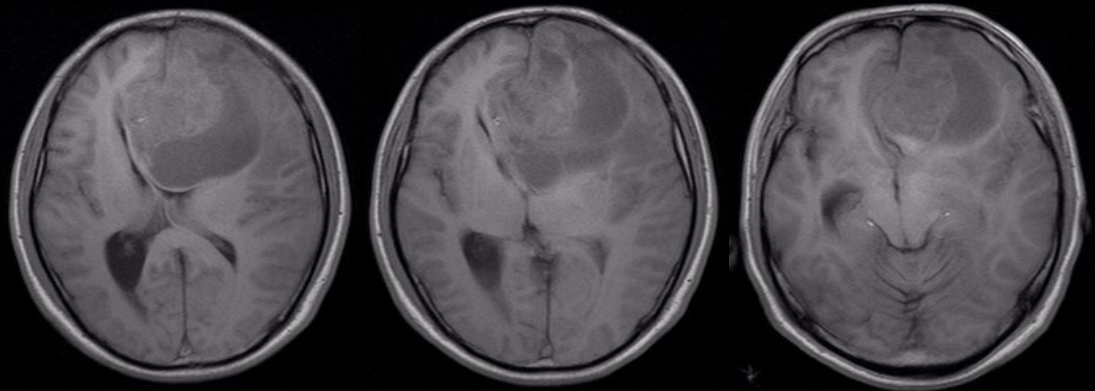

术前头颅MRI平扫加增强